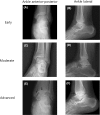

Figure a, b show longitudinal ultrasonographic findings of early hemophilic arthropathy in knee and ankle joint. These demonstrate a small effusion, no fibrotic septa, minimal synovial hypertrophy (<1.5 mm) without flags on PDUS, no hemosiderin deposition and no calcification. The suprapatellar recess (white arrow, a) is minimally distended; Figure c, d show moderate stage of hemophilic arthropathy in knee and ankle joint. These demonstrate a moderate effusion, no fibrotic septa, synovial hypertrophy (1.5–2.5 mm) with 3flags, no hemosiderin deposition and irregular cartilage profile (white arrow, d). Full amount of suprapatellar recess distension (white arrow, c) is observed; Figure e, f show advanced stage of hemophilic arthropathy in knee and ankle joint. These demonstrate a large effusion, no fibrotic septa, synovial hypertrophy (>2.5 mm) with over 3 flags (f), no hemosiderin deposition and cartilage calcification (white arrow, f). Marked distension of the suprapatellar recess with synovium is demonstrated (white arrow, e)